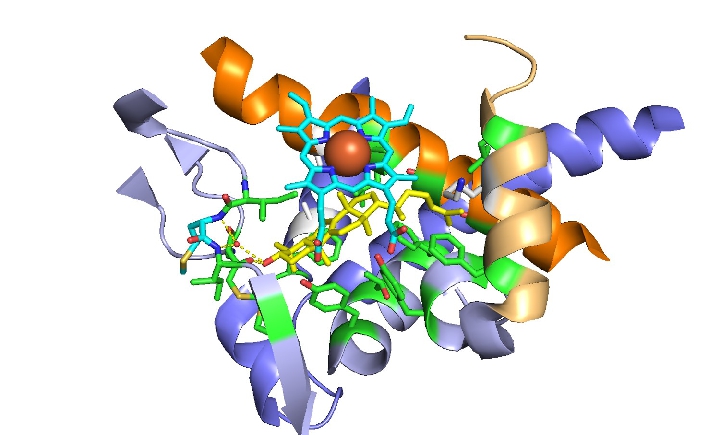

Structure and Function-guided Development of Next-generation Azole Drugs

A disturbing and rapid increase in infections caused by antimycotic-resistant fungal pathogens is one major public health concern facing medicine today. Most severe and fatal cases result from healthcare-associated fungal infections, which are increasingly caused by Candida, Aspergillus and Mucorales. Hence, one significant focus is the investigation of azole and echinocandin resistance in yeasts and moulds and the discovery of new resistance mechanisms. Another major focus is on identifying the underlying mode of amphotericin B resistance in Aspergillus terreus. In this context, we are evaluating mitochondria as crucial modulators of polyene resistance. The mission of HMM is to bridge the translational gap between basic research and the development of novel antifungal drugs. HMM will support epidemiologic, translational and clinical studies to improve the management of fungal diseases.

- Brian Monk, Department of Oral Sciences, Division of Health Sciences, University of Otago, Dunedin, New Zealand